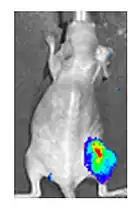

Both in the laboratory and in the clinic it is useful to have a simple means of identifying cells infected by the experimental virus. This can be done by equipping the virus with "reporter genes" not normally present in viral genomes, which encode easily identifiable protein markers. One example of such proteins is GFP (green fluorescent protein) which, when present in infected cells, will cause a fluorescent green light to be emitted when stimulated by blue light.[89][90] An advantage of this method is that it can be used on live cells and in patients with superficial infected lesions, it enables rapid non-invasive confirmation of viral infection.[91] Another example of a visual marker useful in living cells is luciferase, an enzyme from the firefly which in the presence of luciferin, emits light detectable by specialized cameras.[89]

- ^ Yu YA, Shabahang S, Timiryasova TM, Zhang Q, Beltz R, Gentschev I, Goebel W, Szalay AA (March 2004). "Visualization of tumors and metastases in live animals with bacteria and vaccinia virus encoding light-emitting proteins". Nature Biotechnology. 22 (3): 313–20. doi:10.1038/nbt937. PMID 14990953. S2CID 1063835.